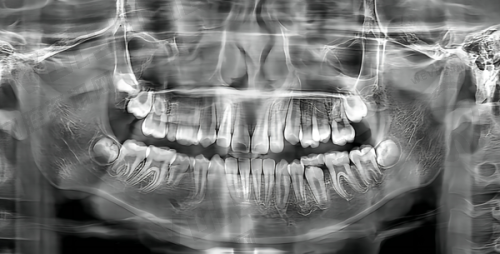

一个真实的实例往往比千言万语更有说服力。一位年龄不大的患者,几年前因右下后牙龋坏拔除后未修复,长期影响咀嚼咬合。术前检查发现患者有牙龈炎症,医生先为其进行了口腔清洁,之后做了种植体植入手术。在愈合后戴基台的过程中,使用了韩国登腾种植体。经过一系列的治疗,患者缺牙部位修复了健康,骨结合良好。患者对治疗成效非常满意,不仅解决了多年来的咀嚼问题,还修复了口腔的美观。这个实例充分展示了海口鼎点口腔在种植牙方面的技术实力和专精水平。